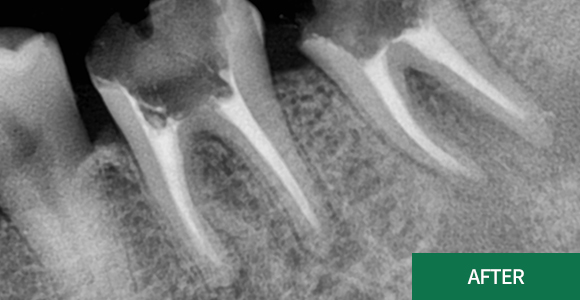

잇몸치료

잇몸치료가 전공 분야인 치주과 원장님께서

꼼꼼하고 꾸준하게 잇몸을 관리해드리고 있습니다.

대학병원에서 주로 시행하는 잇몸 수술까지도 가능한

전문의 원장님과 꾸준한 잇몸관리를 받으시길

바랍니다.